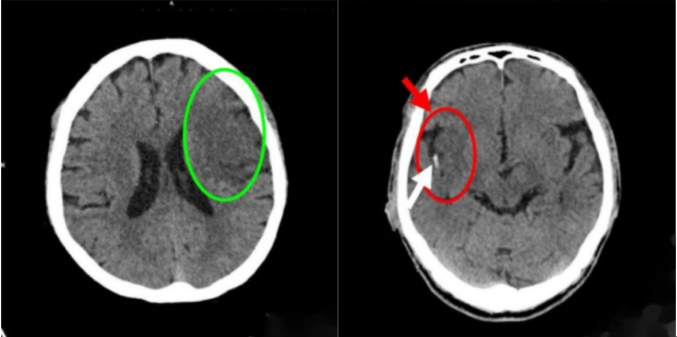

腦出血體積測量

腦梗死快速診斷